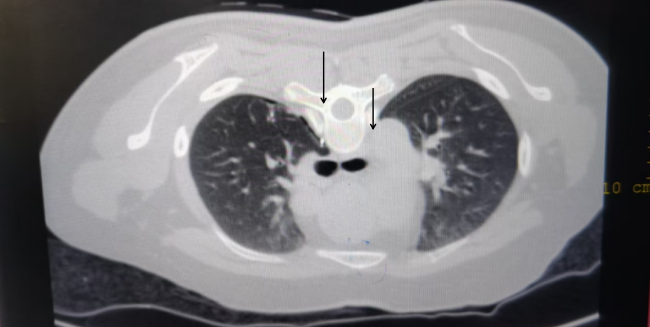

由于患者的磨玻璃结节体积小、密度淡、位置深,传统手术中,医生往往难以通过手指触摸或胸腔镜器械直接定位结节,导致手术难度大、时间长,且易损伤正常肺组织,给医生的手术定位带来了巨大挑战。为解决这一难题,毛宇主任团队引入了CT引导下的“锚定”定位技术。该技术精妙地设计了一套包含穿刺针、推送装置、锚定定位针及定位线的专用系统。术前,团队邀请设备研发人员一起在离体组织上模拟手术,不断进行方案设计,研究具体操作流程,改进技术,减少风险。

准备充分后,于8月23日在医学影像科的支持下,毛宇主任团队为患者进行了肺结节锚定定位术。在CT的精准指引下,医生将定位针插入结节附近(1cm内),完成定位后,撤回穿刺针,通过推送装置将锚定定位针精准地释放并牢固地“锚”定在肺结节旁3毫米周围,这一过程宛如钓鱼高手精准地将鱼钩嵌入鱼儿体内,给隐藏在肺表面下的病灶插上了一面小红旗,实现了对微小肺结节的稳固标记。为后续手术治疗提供了坚实的技术支持,极大地提高了手术的精准度和效率。